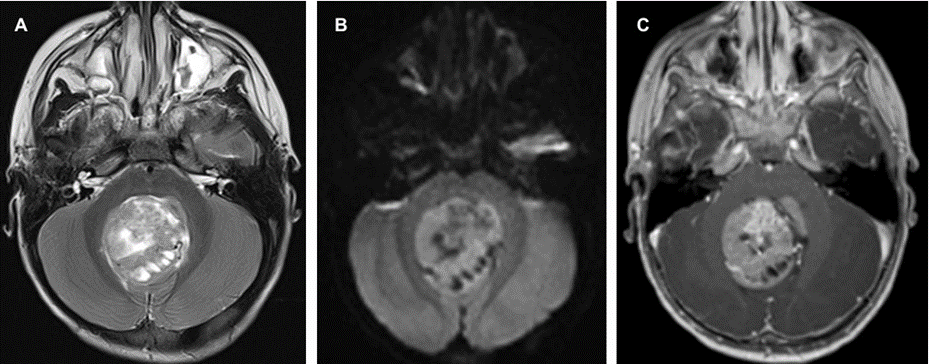

C.T scan was done that revealed hydrocephalus and posterior fossa mass. Subsequent MRI brain showed a large 4th ventricular mass that was predominantly solid with multiple cystic foci, measuring 5 x 4 cm. It exhibited heterogeneous T2 hyperintensity with diffusion restriction and heterogeneous post-contrast enhancement (Figure 1). There were foci of susceptibility on SWI, of calcification and microhemorrhage. There was associated mass effect on the adjacent posterior fossa structures with bilateral cerebellar tonsillar herniation and secondary moderate supratentorial hydrocephalus. There was no other supra or infra tentorial parenchymal or meningeal lesions and no spinal drop metastasis. An EVD tube was inserted through the right frontal approach and steroids were added. Suboccipital craniotomy was performed with total excision of the mass.

Figure 1: Preoperative MRI demonstrating the posterior fossa mass of heterogenous solid and cystic components (a) diffusion restriction on DWI (b) and heterogenous enhancement (c).